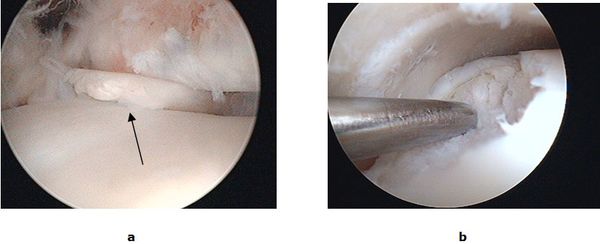

Bei isolierten Knorpel/Knochen Verletzungen (Osteochondrale Läsion, Osteochondrosis dissecans) kann während einer Gelenkspiegelung eine vitalisierende Anbohrung des Knochens erfolgen. Besteht bereits ein ausgeprägter Knorpelschaden wird mit einem speziellen Instrumentarium die harte Knochenschicht durchbrochen und die Bildung von Ersatzknorpel angeregt (Mikrofrakturierung). Der freie Gelenkkörper wird vorher entfernt. Dauerhaft schmerzhafte umschriebene Knorpelläsionen können durch die Verpflanzung eines Knorpel-Knochen-Zylinder (Mosaikplastik, Knorpel-Knochen-Zylinder Transplantation) therapiert werden. Aus einem gesunden nicht belasteten Gelenkanteil wird ein Knorpel-Knochen Zylinder entnommen und in der sog. „Press fit“ Technik am Sprungbein eingesetzt. Ein anderes Verfahren, die sog. MACT eignet sich zur Therapie großer Defektzonen. Bei der MACT (Matrix gekoppelte Autologe Chondrozyten Transplantation) wird Knorpel entnommen und an ein Speziallabor geschickt. Die entscheidenden Zellen werden isoliert, vermehrt und in einer Zweitoperation auf den Knorpeldefekt aufgebracht.

Abb.3: a Gelenkspiegelung mit freiem Gelenkkörper im oberen Sprunggelenk (OSG). b Mikrofrakturierung eines Knorpelulcus am Sprungbein.